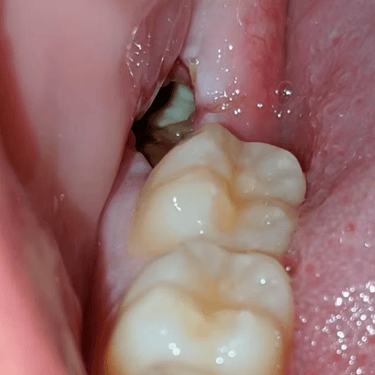

Extracción de Muelas del Juicio

La extracción de las muelas del juicio es un procedimiento quirúrgico para remover los terceros molares que pueden causar dolor, infección o daño a otros dientes debido a su posición o crecimiento anómalo.

Los pacientes pueden experimentar dolor, hinchazón y, en algunos casos, infección alrededor de estas muelas.

El tratamiento incluye la extracción quirúrgica para prevenir o resolver complicaciones.